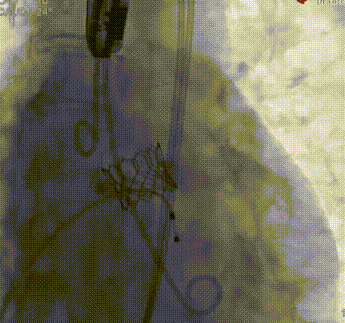

造影下瓣膜定位后,180bp快速起搏下+1cc释放20mm SAPIEN 3瓣膜主动脉;

造影下瓣膜定位

快速起搏下+1cc释放20mm瓣膜

释放后造影及超声评估瓣膜活动良好,轻度瓣周漏;

瓣膜释放后造影评估